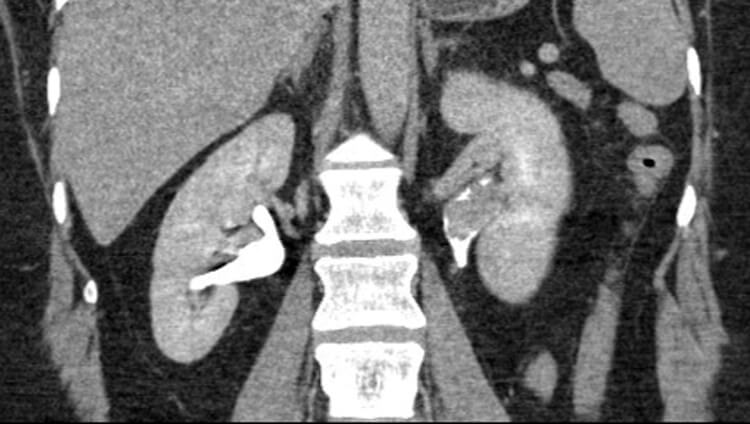

A 64-year-old man presents to the haematuria clinic with visible haematuria, on a background of a 40 pack-year smoking history and family history of bowel cancer in his sister at the age of 48. A CT was performed as part of his investigations (Figure 1).

Figure 1.

Figure 1: Case courtesy of Dr Michael P Hartung, Radiopaedia.org, rID: 78377.

- This is a CT urography (CTU), or CT intravenous urogram (CT-IVU). Most CTU protocols consists of three phases; non-contrast, enhanced / nephrographic, and a delayed / excretory phase. The non-contrast phase is performed prior to contrast administration, the enhanced phase is taken 90-100 seconds after contrast administration and the delayed phase is taken 5-15 minutes after contrast has been given.

- The delayed phase of this CT has demonstrated a filling defect in the left renal pelvis, raising suspicions of UTUC. Other common differential diagnosis includes centrally located renal cancer, benign tumours (e.g. fibroepithelial polyps, nephrogenic adenomas), papillary necrosis, and blood clot.